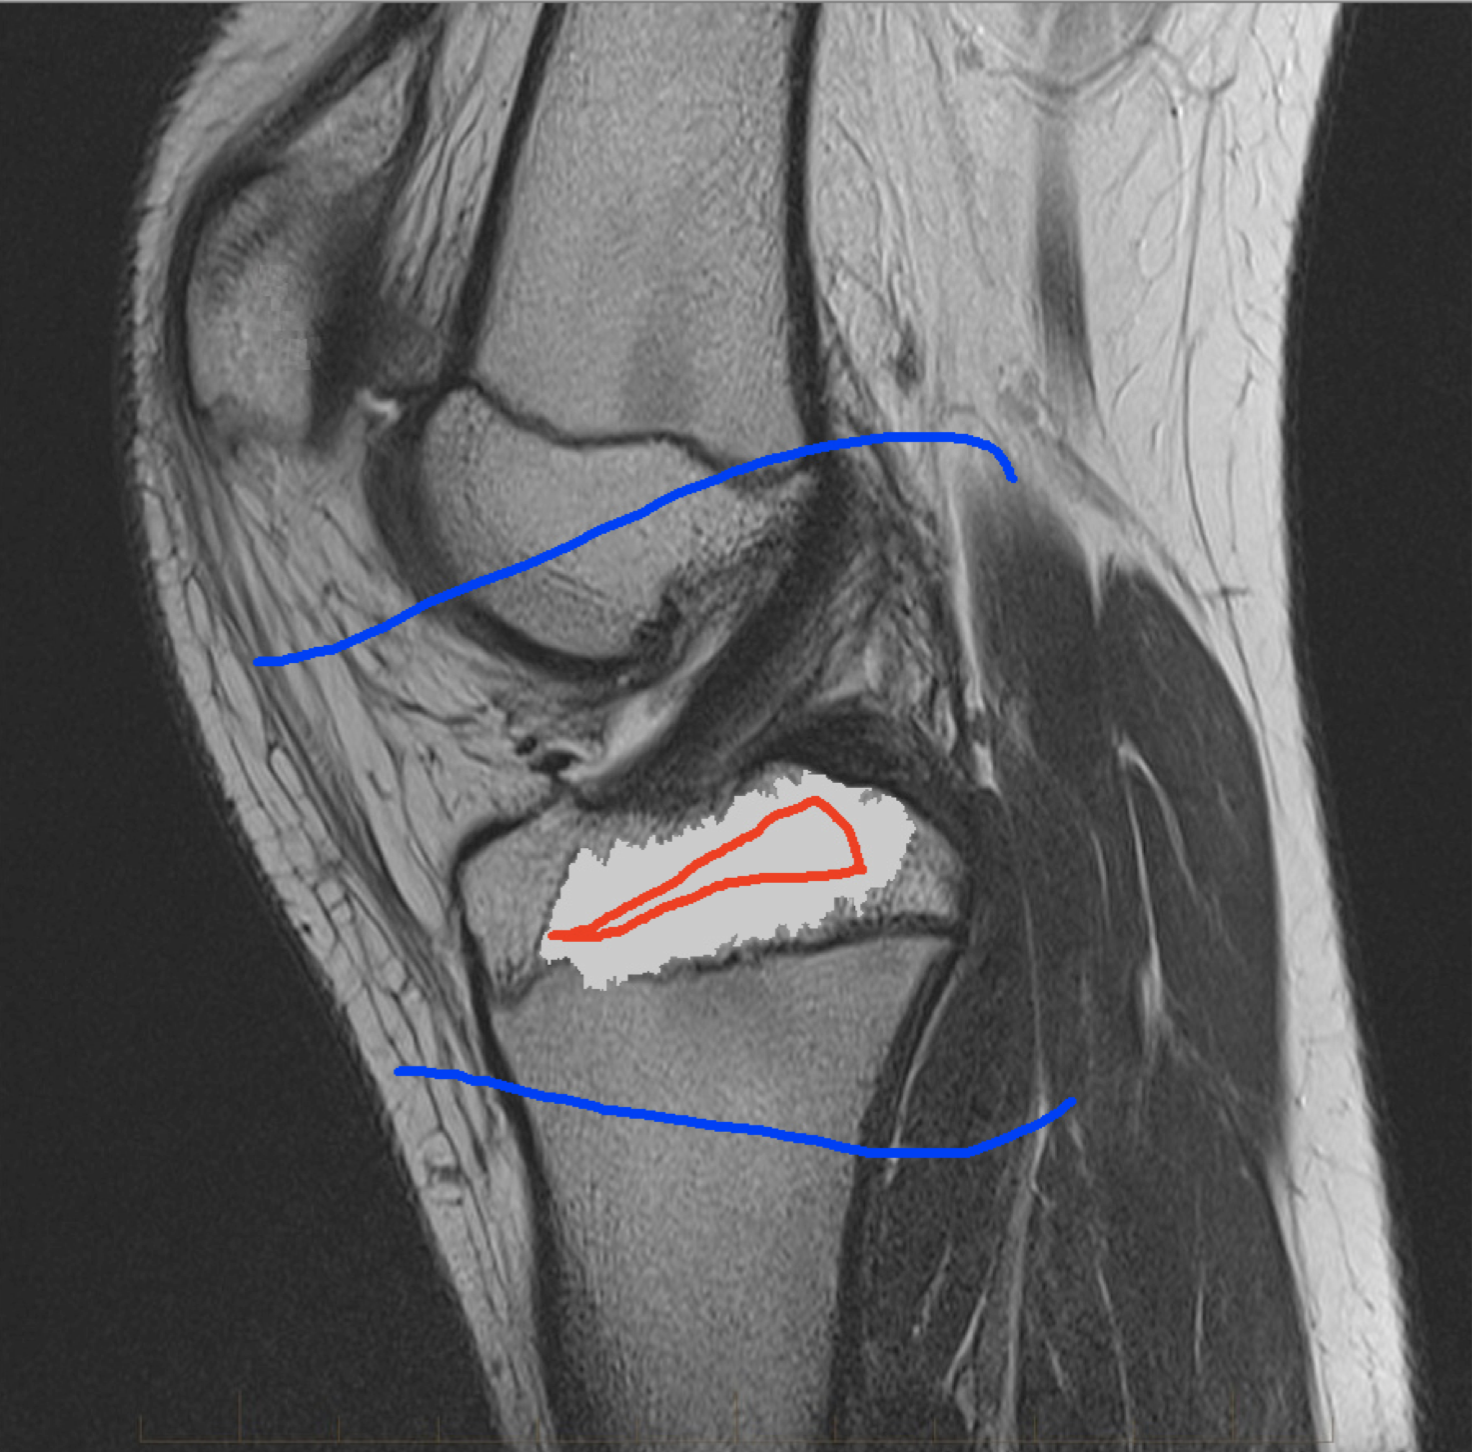

Four sets of test results are shown below. In Test 1 we compare models M1 – M6 to the proposed model M7 for two images which are hard to segment. The first is a CT scan from which we would like to segment the lower portion of the heart, the second is an MRI scan of a knee and we would like to segment the top of the Tibia. See Figure 9 for the test images and the marker sets used in the experiments. In Test 2 we will review the sensitivity of the proposed model to the main parameters. In Test 3 we will give several results achieved by the model using marker and anti-marker sets. In Test 4 we show the initialisation independence and marker independence of the Geodesic Model on real images.

Refer to captionRefer to captionRefer to captionRefer to caption

(i)                                 (ii)                                 (iii)                                 (iv)

Figure 9: Test 1 setting: (i) Image 1;  (ii) Image 1 with marker and anti-marker set shown in green and pink respectively;  (iii) Test Image 2; (iv) Image 2 with marker set shown.

Refer to caption

(a) M1 (Left to right:) Test Image 2 with markers (red) and anti-markers (blue), foreground segmentation and background segmentation (we used published software, no parameter choice required).

(b) M2 λ=1𝜆1\lambda=1, γ=15𝛾15\gamma=15.

(c) M3 λ=5𝜆5\lambda=5, θ=1𝜃1\theta=1.

(d) M4 λ=1/8𝜆18\lambda=1/8.

(e) M5 λ=1,γ=15,θ=110formulae-sequence𝜆1formulae-sequence𝛾15𝜃110\lambda=1,\gamma=15,\theta=\frac{1}{10}.

(f) M6 λ=15,θ=1formulae-sequence𝜆15𝜃1\lambda=15,\theta=1.

(g) M7 λ=10,θ=1formulae-sequence𝜆10𝜃1\lambda=10,\theta=1.

Figure 11: Visual comparison of M1 – M7 results for Test Image 2. M1 segmented part of the object, M2 – M4 failed to segment the object, M5, M6 and M7 correctly segmented the object.